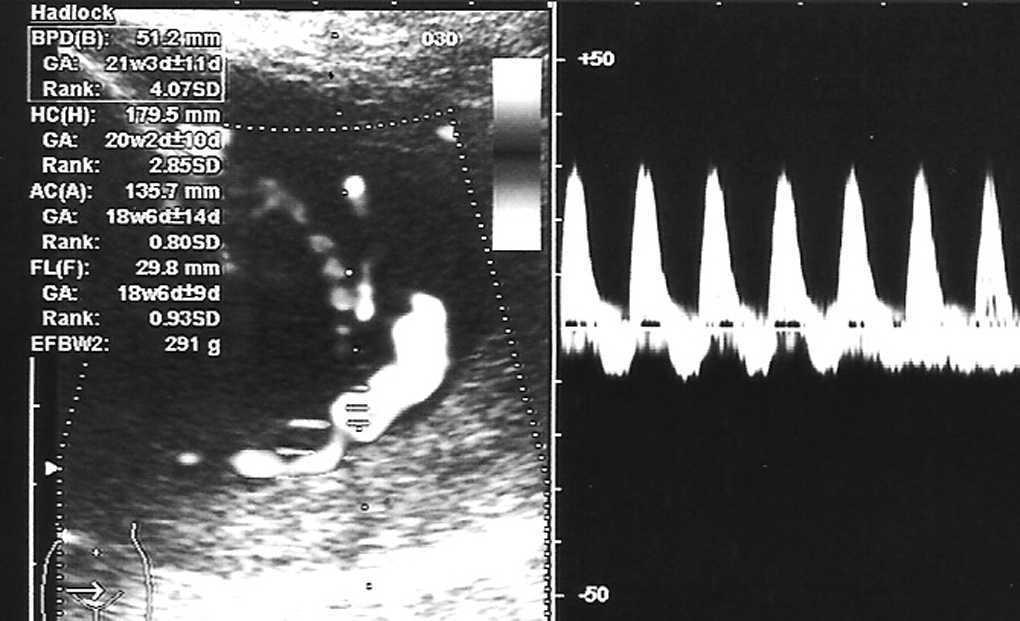

Octavigesta de 41 años, con embarazo no controlado, a quien en la semana 20 se objetiva un feto con somatometría y peso correspondientes a 17-18 semanas; la paciente no acudió a posteriores controles y rechazó la posibilidad de técnica invasiva para estudio de cariotipo. En semana 25 + 5 se remite a la unidad de medicina maternofetal con el diagnóstico de retraso de crecimiento intrauterino (RCIU) precoz y severo. En el estudio realizado se objetiva un feto en cefálica con diámetro biparietal (DBP) de 51,2 mm, circunferencia craneal (HC) de 179,5 mm, circunferencia abdominal (AC) de 135,7 mm y longitud femoral (LF) de 29,8 mm, con peso fetal estimado (PFE) de 291 g, muy por debajo de los percentiles (menor de percentil 3) para 25-26 semanas de embarazo (fig. 1). Presentaba una placentomegalia importante y un estudio Doppler con una onda de velocidad flujo (OVF) en arteria umbilical patológica con ausencia de diástole y flujo reverso (fig. 2). Inicio de distribución de flujo en arteria cerebral media y conservaba flujos venosos. Oligoamnios prácticamente total. Con el diagnóstico de RCIU severo precoz con signos de insuficiencia placentaria, se explicó la situación a la paciente y se realizó estudio para cariotipo con QF-PCR, que estaba dentro de la normalidad. En posterior control ecográfico, no se evidenció la presencia de latido cardíaco fetal, y se confirmó el óbito del feto. En ese control, la paciente refería inicio de lesiones cutáneas en miembros inferiores intensamente pruriginosas. Tras administrar dinoprostona local se produjo la expulsión de un feto de 301 g y posterior legrado sin incidencias. En los días posteriores, el cuadro cutáneo progresó de forma acelerada desde los miembros inferiores a abdomen, miembros superiores, cuello, cabeza, boca, manos y pies; únicamente respetaba la cara (figs. 3-5). Se realizó biopsia de dichas lesiones que informó de la existencia de depósitos lineales de la fracción del complemento C3 y de IgG en la membrana basal de la piel afectada y en zonas perilesionales, compatible con un cuadro de HG.

Figura 1.Retraso del crecimiento fetal severo y precoz.

Figura 2.Onda de velocidad de flujo umbilical patológica con ausencia de diástole y flujo reverso.